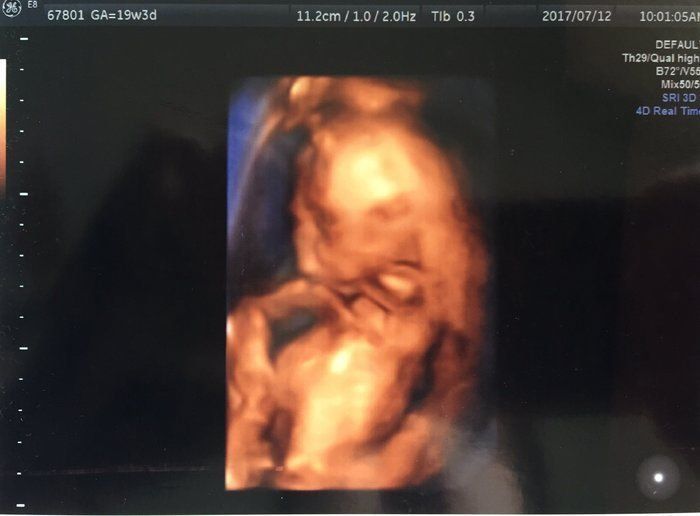

宮本真知さんの妊娠19週目のエコー写真

親戚の結婚式へ出席するなど、この時期は安定した状態が続きました。今回は4Dエコーでした。これは一部を切り取った写真なのですが、実際は、赤ちゃんがリアルタイムに動いているところを、立体的な画像で見ることができます。最初は手で顔を隠していたわが子。親孝行なことに、4Dで様子を見ている最中に腕を動かして顔を見せてくれました。気になる性別は、股をがっちり閉じていて分かりませんでした。顔もお尻も隠して「恥じらいがある」と先生に褒めて(?)頂きました。